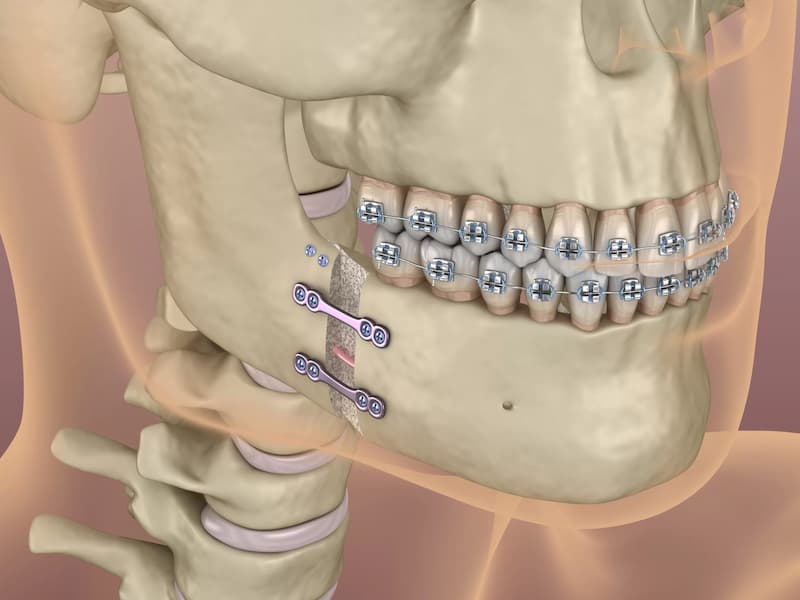

۱. استحکام: ایمپلنت جراح فکی با استفاده از یک فیکسچر وارد شده در آب مشترک فک در بیشتر موارد استحکام بالایی به دندان مصنوعی می دهد.

۳. ماندگاری: ایمپلنت جراح فک بعد از جایگزینی به طور دائمی در دهان باقی می ماند و نیازی به خارج کردن و نصب مجدد ندارد.

۳. عوارض: در برخی از موارد، عوارض مانند خونریزی، عفونت، و ترک خاصی در استخوان پایه ممکن است رخ دهند.